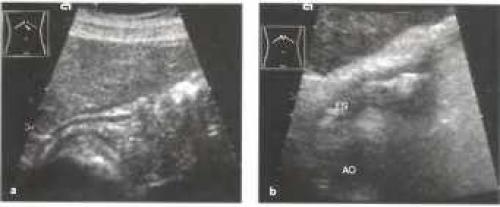

К структурам, которые, как правило, хорошо видны при ультразвуковом исследовании, относятся кардия и гастроэзофагеальный переход, антральный отдел желудка, а также двенадцатиперстная кишка. При этом печень играет роль ультразвукового окна. Качество же визуализации дна и тела желудка спереди или через селезенку (ультразвуковое окно) оставляет желать лучшего. Кардиальный отдел желудка чаще и лучше всего удается визуализировать на продольном сечении, когда желудок определяется между печенью и аортой.

Рис. 3. Визуализация гастроэзофагеального перехода на продольном сечении

Рис. 4. Визуализация гастроэзофагеального перехода на поперечном сечении: Виден срез тела желудка, заполненного неоднородным содержимым (v

В качестве примера патологии кардиального отдела желудка, выявляемой сонографически можно привести его карциному (Рис 5).

Рис 5. а, b Гастроэзофагеальное сочленение (включает кардиальный отдел и входной отдел желудка), а На снимке в косой продольной плоскости, проходящей через верхнюю часть брюшной полости, определяется нормальная гипоэхогенная стенка (мышечный слой) кардиального отдела и свода желудка, b Карцинома кардиального отдела желудка: неправильной формы, гипоэхогенное опухолевое образование, продолжающееся от кардиального отдела пищевода (ES) до свода желудка (F). АО - аорта.